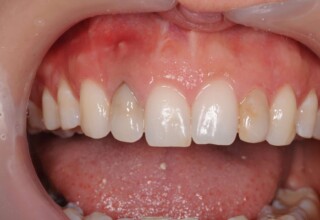

Composite Resin Veneers

Resin veneers are an inexpensive mode of esthetic improvement of anterior teeth, premolars also. Their potential is admirable and their limit is the operator’s clinical dexterity and imagination. In this case there were multiple problems with the upper four incisors: staining, poor inclinations, diastemas, multishading, poor interrelationship and poor tooth-gingiva ratios. They were restored with four direct composite resin veneers (one on a porcelain implant crown!) which were manufactured intraorally!!!